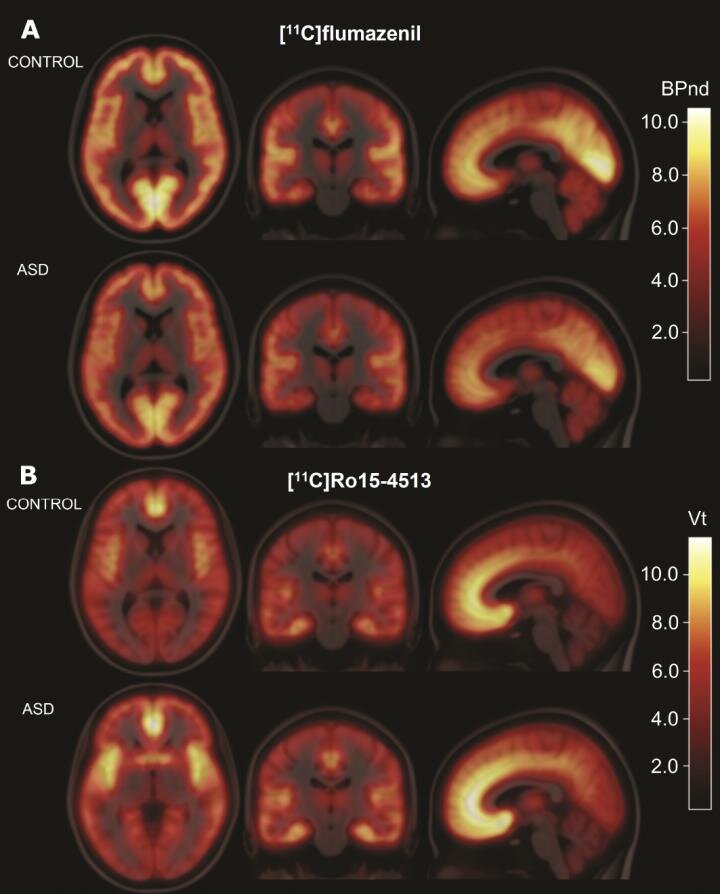

Как известно, одной из самых распространённых гипотез, объясняющих аутизм, является то, что это состояние связано с дисбалансом между возбуждающей глутаматной и тормозной ГАМК-нейротрансмиссией в головном мозге (мы помним, что гамма-аминомасляная кислота, она же ГАМК, она же GABA — главный тормозной нейромедиатор в мозге). Однако статья, вышедшая в журнале Science Translational Medicine, показывает несколько обескураживающие результаты ПЭТ-сканирования (о том, что такое ПЭТ, читайте в отдельной статье) больных аутизмом по сравнению с контролем. Две разных молекулы-трейсера GABAА-рецепторов не показали никакой разницы в плотности больных с расстройством аутистического спектра взрослых и группы здорового контроля. Та же самая история случилась с тремя (!) мышиными моделями аутизма. Подробности — в ближайшие дни. Credit: J. Horder et al., Science Translational Medicine (2018)

Credit: J. Horder et al., Science Translational Medicine (2018)